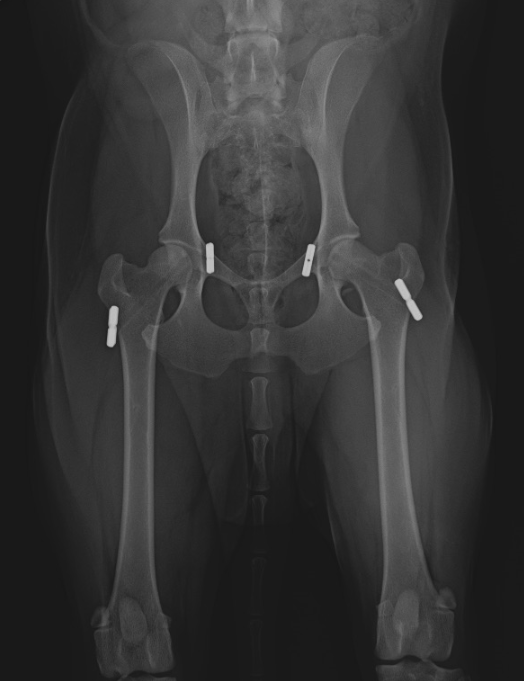

We look at the causes, symptoms and treatment of hip luxation in dogs, as well as what factors might predispose a dog to this health issue. Then, i’ll explain in which part of the life cycle each condition usually occurs. In this article, we’ll go through common hip conditions you might see in your dog so you understand the signs, preventative measures, and treatments. dislocation often occurs due to physical trauma, but some dogs are more susceptible to this problem than others. Look for key clinical signs, such as: if a dog has dislocation of the hip, you might be able to tell by observing their leg. In this article, you will learn what causes hip pain in dogs, signs of hip pain to recognize, when to seek help from your veterinarian, and how you can help your dog with hip pain at home. There are two main approaches to. At animalwised, we explain why my dog has a dislocated hip. if you suspect that your dog has dislocated their hip, take them immediately to the emergency vet.